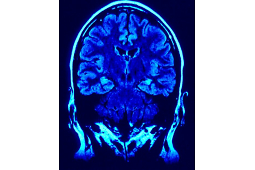

Światowy Dzień Chorych na Chorobę Parkinsona stanowi pretekst do poszerzania wiedzy na temat choroby i sytuacji pacjentów. Choroba Parkinsona, czyli postępujące schorzenie mózgu, objawia się w początkowym stadium drżeniem kończyn, spowolnieniem ruchowym, czy sztywnością mięśni. Wraz z postępem choroby, pacjent odczuwa coraz więcej dolegliwości, które ograniczają jego sprawność ruchową, uniemożliwiając pracę, a z czasem, również najprostsze, codzienne czynności. Klasyczne objawy zewnętrzne choroby to m.in. spowolnienie, sztywność mięśni, czy też drżenie kończyn w spoczynku.

– Nie istnieje terapia przyczynowa, która zahamowałaby dalszy rozwój choroby. Stosowane leczenie objawowe pozwala pacjentom na optymalne funkcjonowanie przez wiele lat. Niestety stały postęp choroby sprawia, że po pewnym czasie leki doustne i rehabilitacja nie są już tak skuteczne jak wcześniej. Wówczas u pacjentów można rozważyć zastosowanie jednej z zaawansowanych terapii: chirurgiczną (DBS) lub infuzyjną (wlew podskórny apomorfiny lub dojelitowy duodopy). W Polsce jedyną dostępną i refundowaną metodą jest tylko metoda operacyjna – głęboka stymulacja mózgu (DBS, deep brain stimulation), polegająca na umieszczeniu elektrod w wybranych strukturach mózgu, w efekcie czego możliwe jest modyfikowanie ich czynności odpowiednio do stanu pacjenta. Efekty są widoczne prawie zaraz po operacji – mówi prof. Andrzej Bogucki, prezes Polskiego Towarzystwa Choroby Parkinsona i Innych Zaburzeń Ruchowych.

Metoda głębokiej stymulacji mózgu skutecznie redukuje nasilenie zaburzeń ruchowych typowych dla zaawansowanego stadium choroby, umożliwiając pacjentom samodzielne funkcjonowanie lub nawet powrót do pracy.